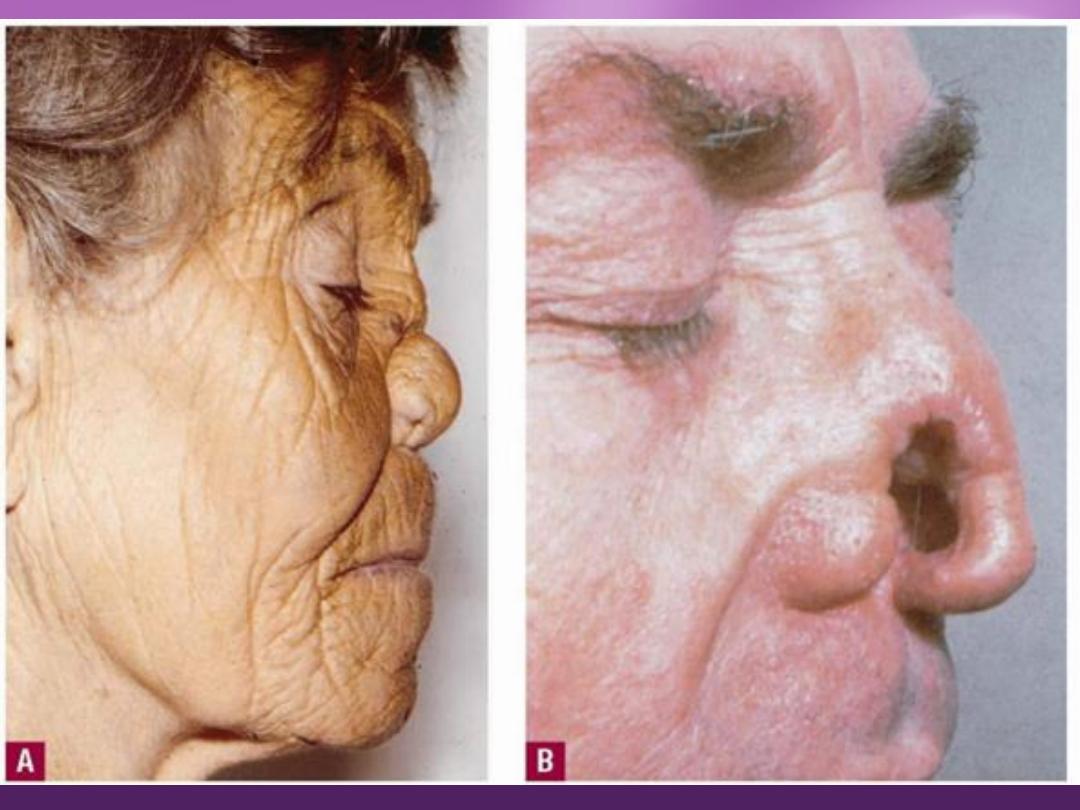

MM Lesions:

palate, nasal mucosa, tongue, tonsils, and pharynx

(

saddle nose

) are the disease hallmark.

3. Nose: saddle nose.